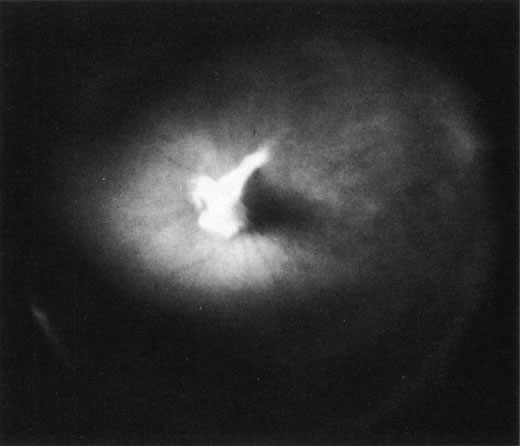

The retina is usually not involved in anterior PHPV. Indeed, previous studies have suggested that the anterior form is due to a primary defect in lens development and that vitreous changes are all secondary.34 This postulate has never been substantiated. There are rare instances of posterior PHPV in which opaque connective tissue arises from Bergmeister's papilla and persistent hyaloid vessels (Fig. 1).32,35 These can cause congenital falciform folds of the retina and, if severe, can cause tentlike retinal folds, leading on rare occasions to tractional and/or rhegmatogenous retinal detachment. Font and investigators36 demonstrated the presence of adipose tissue, smooth muscle, and cartilage within the retrolental plaque and suggested that PHPV arises from metaplasia of mesenchymal elements in the primary vitreous.